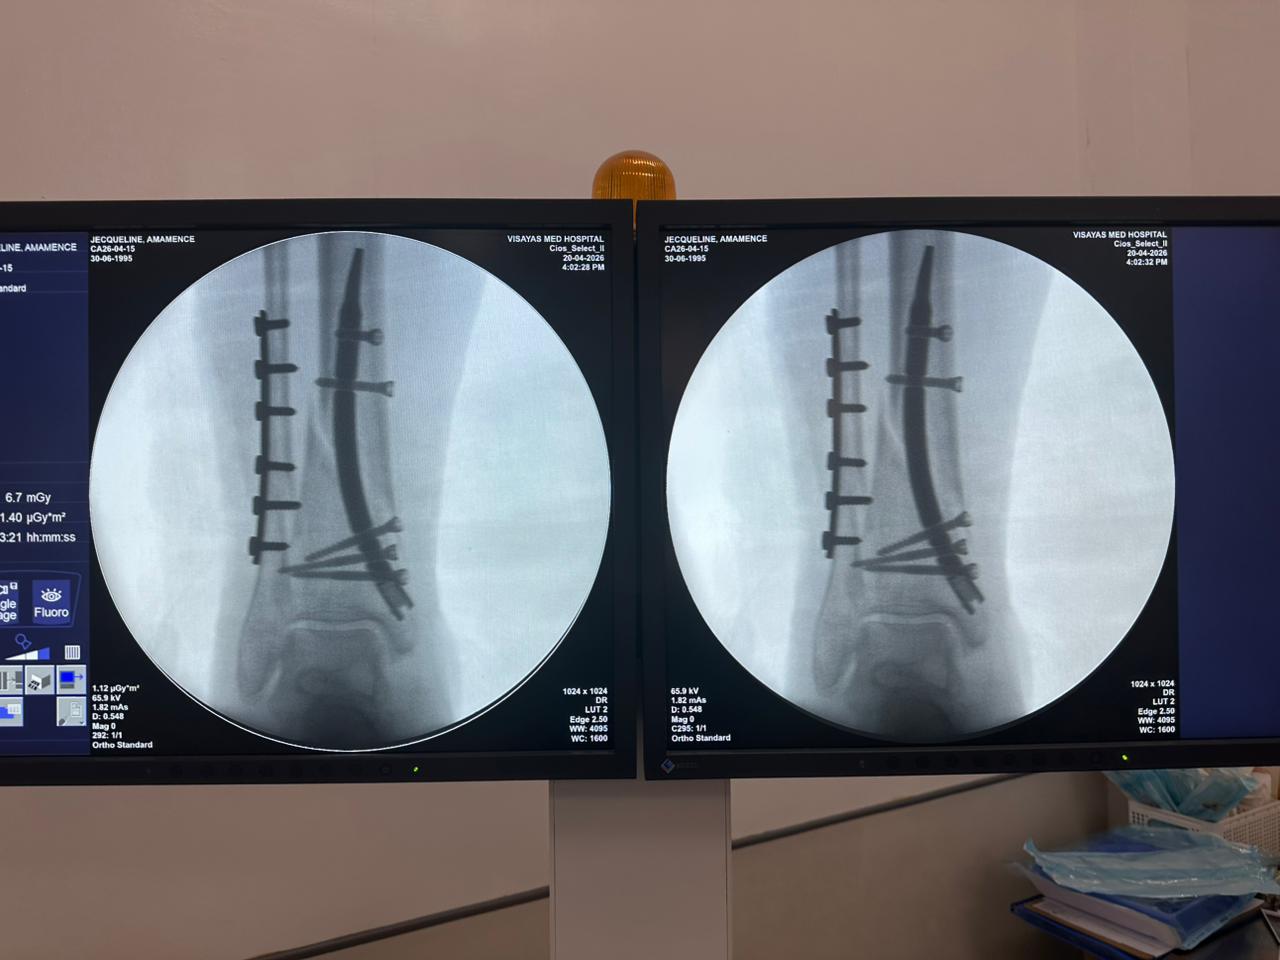

Estudio de caso de fijación de clavo tibial distal con soporte de placa para peroné

Tibia y peroné distales

Clavo tibial distal

Placa de bloqueo del peroné

Radioscopia intraoperatoria con arco en C, vistas AP y lateral

Este caso involucró la fijación de la tibia distal utilizando un clavo tibial distal intramedular. La fluoroscopia intraoperatoria confirmó la posición del clavo, los tornillos de bloqueo distales y la fijación de la placa del peroné.

clavo-tibial-distal-fluoroscopia-intraoperatoria-czmeditech (2)

clavo-tibial-distal-fluoroscopia-intraoperatoria-czmeditech (3)